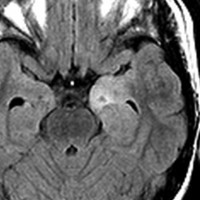

7才の時に音読でつかえるようになり,眼で何かを追っているような欠伸発作(左側頭葉てんかん)を繰り返すようになり,強直間代発作を生じて腫瘍が発見されました。下側頭回底面の皮質に発生した境界明瞭な腫瘍であり,周囲に脳浮腫を伴っています。T2強調画像で線維成分の多い硬い部分は低信号に,軟らかい部分はやや高信号となり,ガドリニウムでheterogenousに増強されます。グレード1の神経節膠腫としては非典型的な画像所見で術前診断は難しいもので,PXA pleomorphic xanthoastrocytoma も疑いました。もちろん治療としては開頭手術での全摘出です。術後に発作は消失しています。